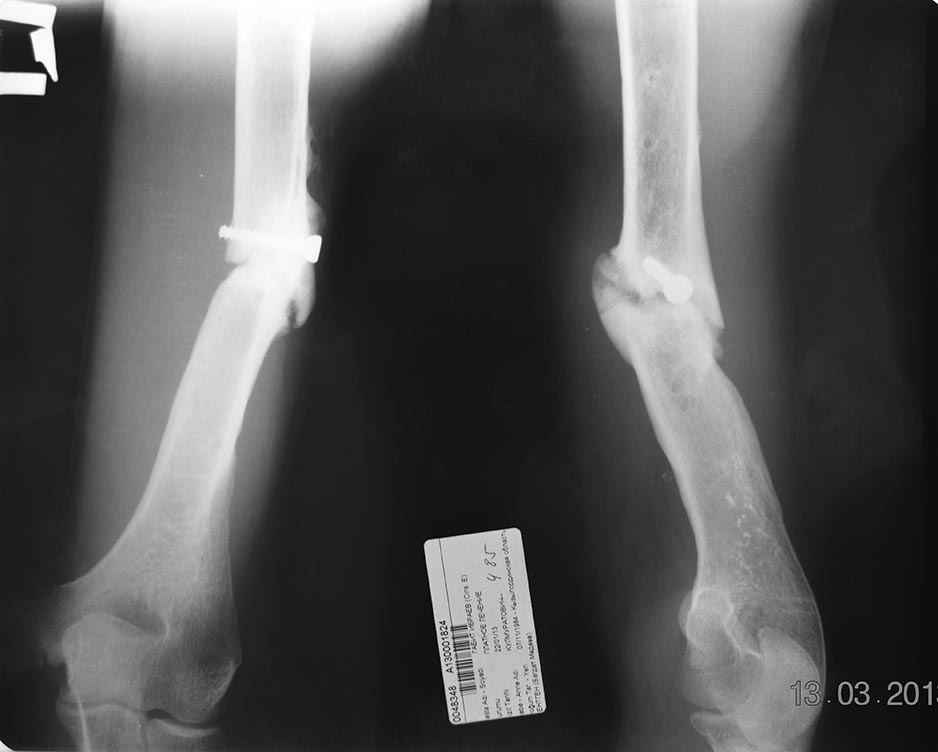

Уважаемые коллеги! Пациент Г 29 лет. 2009 году оперирован в одной из ЦРБ с диагнозом закрытый перелом средний трети плечевой кости.

Произведена открытая репозиция, экстрамедуллярный некорректный металлоостеосинтез (фиксация 4 винтами). 2010 году в ОКБ по поводу ложного сустава и нестабильностью металлоконструкции произведено ЧКДО аппаратам Илизарова +костная аутопластика. В данный момент имеется угловая деформация плеча и незн болезненность в проекции деформации. Клинический признаки воспаления и потологический подвижность нет, но рентгенологический признаки слабой консолидации и угловой деформации.

Планируем удаление винта, рассверливание КМК, БИОС плечевой кости + аутопластика.